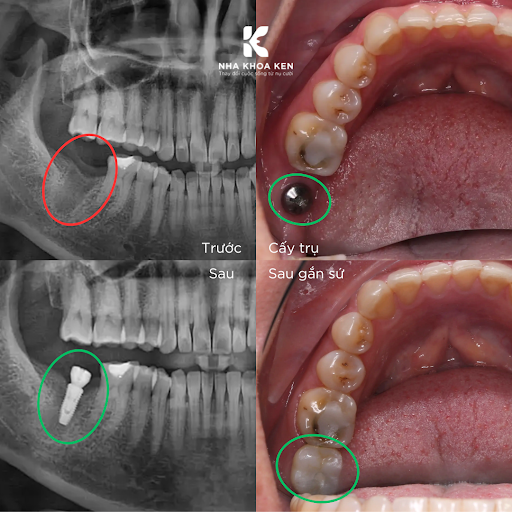

Theo đó, trồng răng Implant là một tiểu phẫu được thực hiện bằng cách cấy ghép chân răng nhân tạo bằng chất liệu Titanium vào trong xương hàm nhằm thay thế những răng đã mất. Sau một thời gian , răng sứ giống như răng thật sẽ được gắn trên trụ Implant, với chức năng và hình thể không khác gì răng thật.

- Sau khi trụ implant đã tích hợp trong xương hàm, bác sĩ sẽ lắp răng sứ lên trên để hoàn thiện.